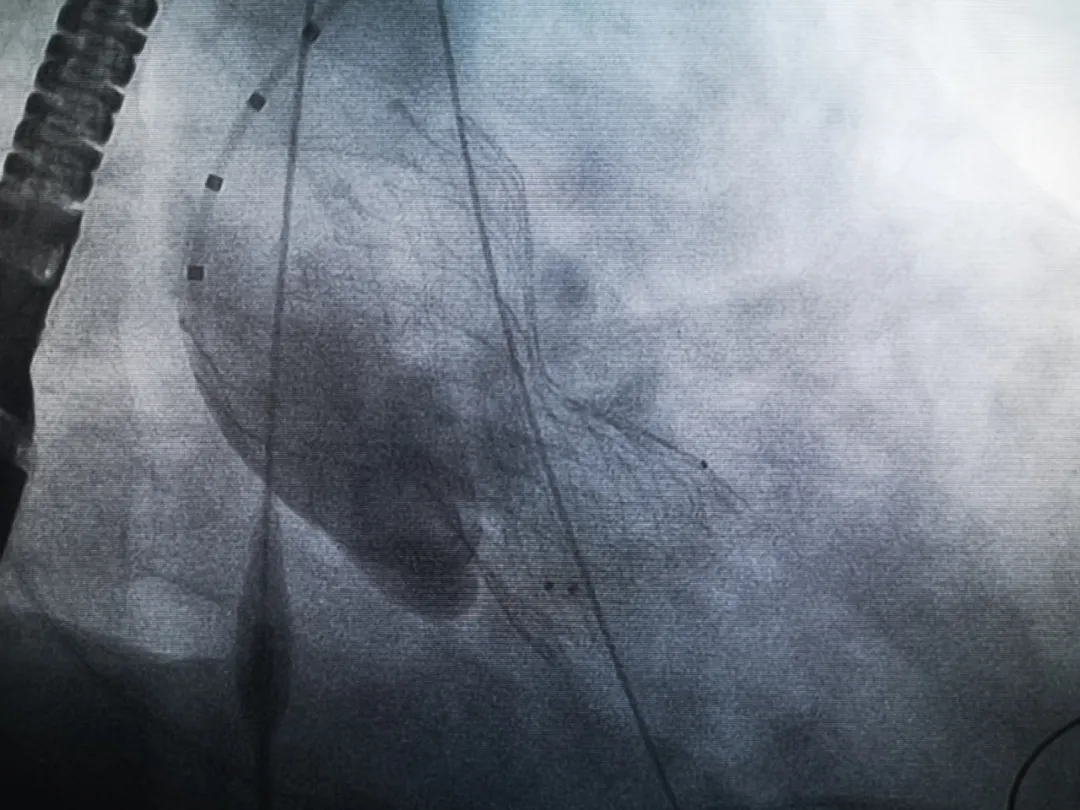

王子的手術(shù)被安排在周五。術(shù)前一天,TAVR團(tuán)隊(duì)再次碰頭討論,從麻醉中血壓控制、球囊擴(kuò)張、瓣膜釋放,到各種可能突發(fā)狀況的應(yīng)對(duì),都提前制定了方案。尤其是瓣膜鈣化極為嚴(yán)重,對(duì)于擴(kuò)張球囊型號(hào)的選擇、擴(kuò)張的力度以及瓣膜植入后瓣周漏的發(fā)生預(yù)測(cè),都具有很大挑戰(zhàn)。然而,如果沒有這些挑戰(zhàn),他又何必選擇我們呢!

手術(shù)過程緊張而有序,心臟沒有停跳,也沒有太大的血壓波動(dòng);球囊擴(kuò)張的恰到好處,瓣膜釋放之后超聲醫(yī)生的評(píng)估是至關(guān)重要的,因?yàn)槲覀兲崆熬蜏?zhǔn)備了后擴(kuò)張,也準(zhǔn)備了瓣中瓣,甚至還準(zhǔn)備了瓣周漏封堵。所幸的是,超聲診療中心劉夢(mèng)梅醫(yī)生說:沒有返流、沒有瓣周漏,瓣膜形態(tài)良好,跨瓣壓差約17mmHg(相較于術(shù)前的87mmHg還是可以接受的)。瓣膜置入的成功并不是慶祝的時(shí)候,從戰(zhàn)場(chǎng)撤退仍然需要謹(jǐn)慎。由于王子特別胖,腹股溝區(qū)脂肪尤為肥厚,在股動(dòng)脈插管拔除、確認(rèn)搏動(dòng)正常之后,便逐層縫合。同時(shí)為了美觀、縫合之后不至于鼓個(gè)包出來,我們又仔細(xì)剪除了部分脂肪。術(shù)后次日,王子便可以下床活動(dòng)了。